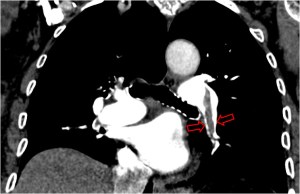

SIGNO DE LAS CRURAS O DEL PILAR DIAFRAGMÁTICO DESPLAZADO

Cuando en la TC vemos que las cruras diafragmáticas están desplazadas lejos de la columna por líquido, éste está situado en la cavidad pleural (flecha). El líquido intraabdominal, a diferencia del derrame pleural, se sitúa lateral y anterior a las cruras.